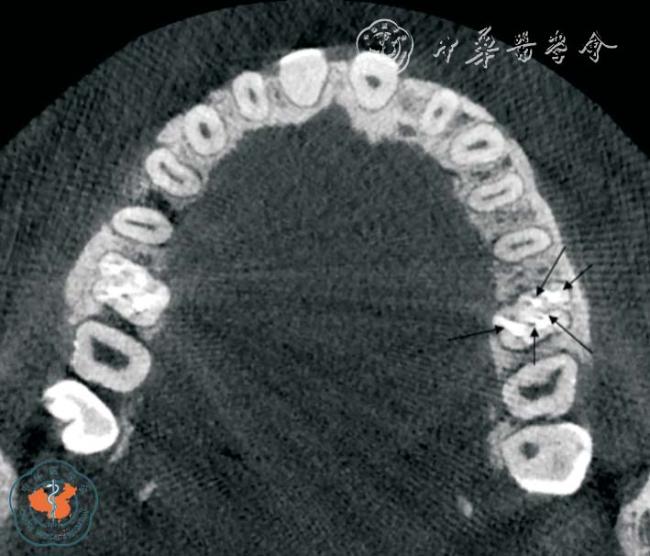

图2 CBCT 轴位、VR 及MPR 重建冠、矢状位图像显示上颌中切牙变异根管